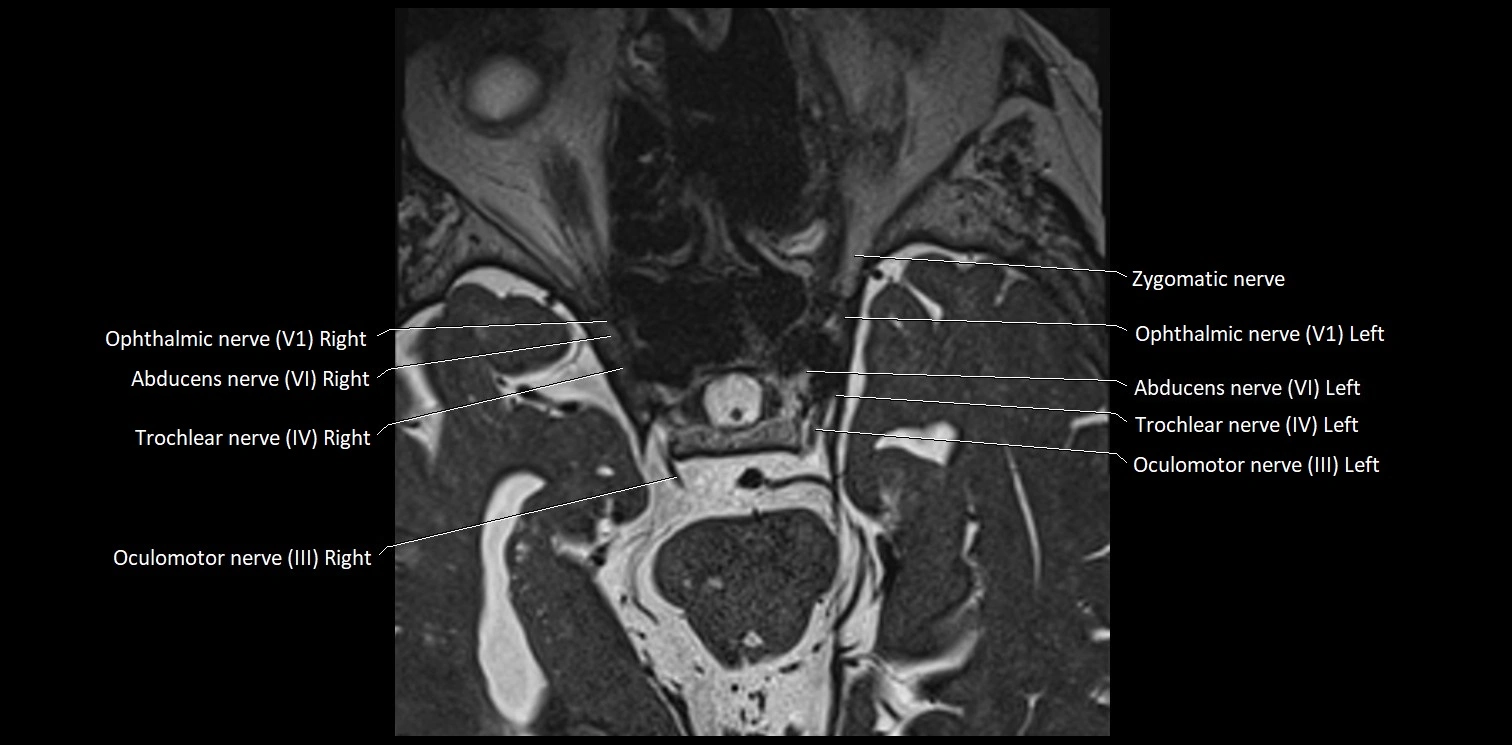

MRI Appearance

• The abducens nerve is a small, thin, linear structure

• Best visualized on high-resolution T2-weighted 3D MRI sequences (e.g., FIESTA or CISS)

• Seen as a hypointense (dark) line running from the brainstem at the pontomedullary junction, traversing the prepontine cistern, and entering Dorello’s canal under the petrosphenoidal ligament, then into the cavernous sinus, and finally the orbit

• May be challenging to visualize in standard MRI due to its small size

• Pathology may be inferred by absence, displacement, or enhancement of the nerve

MRI images

image